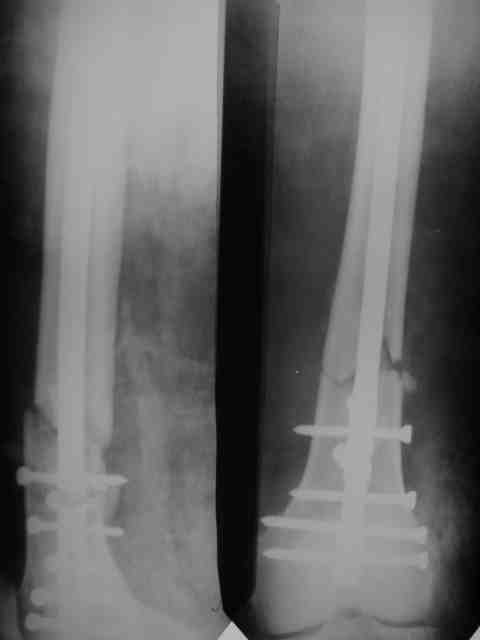

Рг в приложении.

КАН> допущенные ошибки. Спасибо. Рг в приложении.

Снимки вполне симпатичные. Единственное, по ротации не понял, уж больно неразборчивый тот, который без гвоздя.